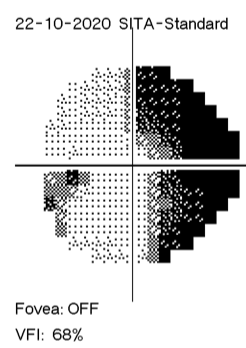

It is hard to explain how I see compared with how someone else sees when I don’t know differently. My visual is shown in the photographs below – this is my left eye (central 30 degrees) with darker areas representing field loss. The photo on the left is six months ago, and the photo on the right was around a week ago. I did not realise just how much had changed until putting these two photos side by side last week.